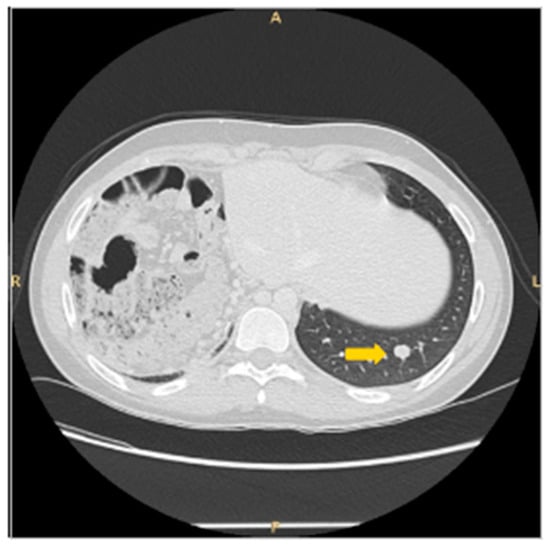

2. Patient Information, Clinical Findings and Diagnostic Assessment

3. Therapeutic Intervention and Outcome